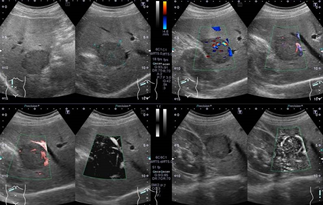

高周波数の音波を腹部にあて、臓器の状態を調べる検査です。心臓や肝臓、胆嚢、膵臓、腎臓、脾臓、乳腺の様子を観察することができます。検査は、X線検査でないので、「被ばく」もなく安全な検査です。

造影検査等の最新技術を用いた精密検査も積極的に行っています。